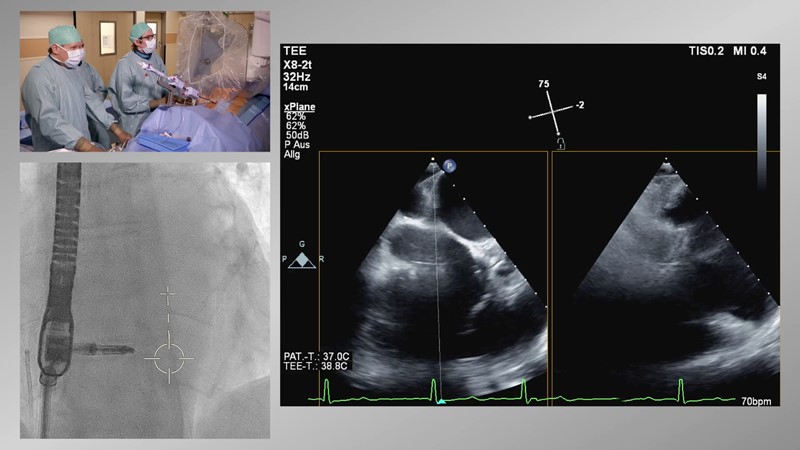

- To learn how will product innovation (Mitraclip NTR / XTR) drive improvement in procedural and clinical outcomes (EXPAND)